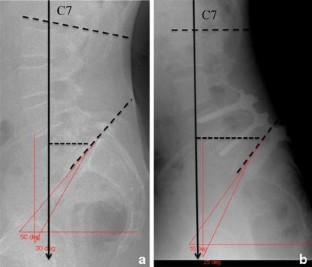

Significant improvement toward more normal values for PT and SS in relation to PI was observed after surgery. Pelvic incidence was unaffected by surgery. Correction of the spinosacral angle shows that the anterior tilt with anterior sagittal imbalance due to spondylolisthesis may be corrected by reduction and fusion of the slipped level. Functional outcome was satisfactory with a statistically significant difference between preoperative values and final follow-up values. The sub-group of patients with insufficient restoration of sagittal balance parameters had less good outcomes than the others.

Surgical management of low- and mid-grade isthmic spondylolisthesis showed good clinical outcome with restoration of correct values for the pelvic position-dependent parameters, i.e., pelvis tilt, sacral slope, C7 plumb line position and SSA.